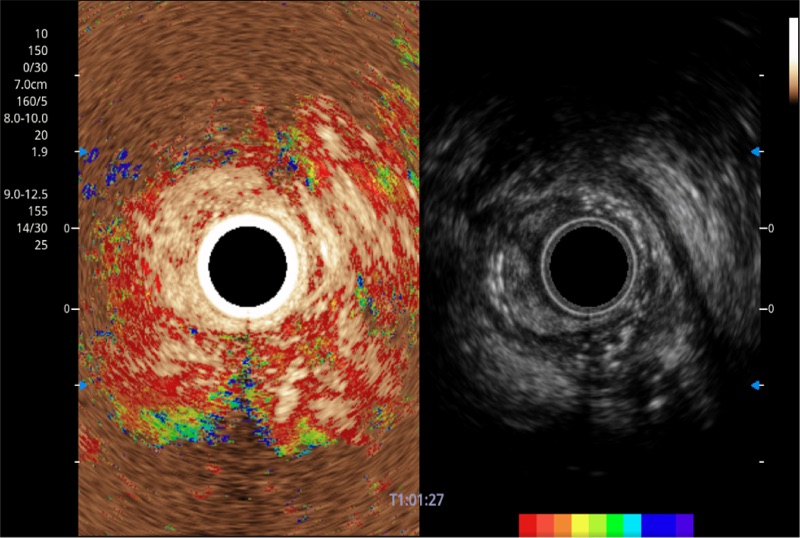

可人为将灰阶图像转变成彩色的显示方式,增强人眼对于不同回声强度的敏感度,主观上增加了图像分辨率

肝左叶和肝静脉的横截面